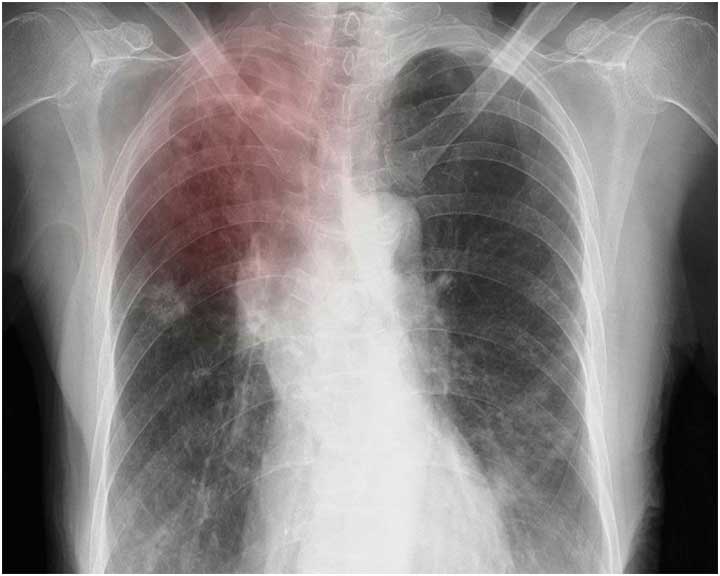

Image

An X-ray scan of a pair of lungs that are affected by tuberculosis.

Better Tests and Kinder, Quicker Cures

More than a million people die each year from tuberculosis, including Americans. UCSF researchers are developing new treatments and early diagnostics to fight TB at home and abroad.